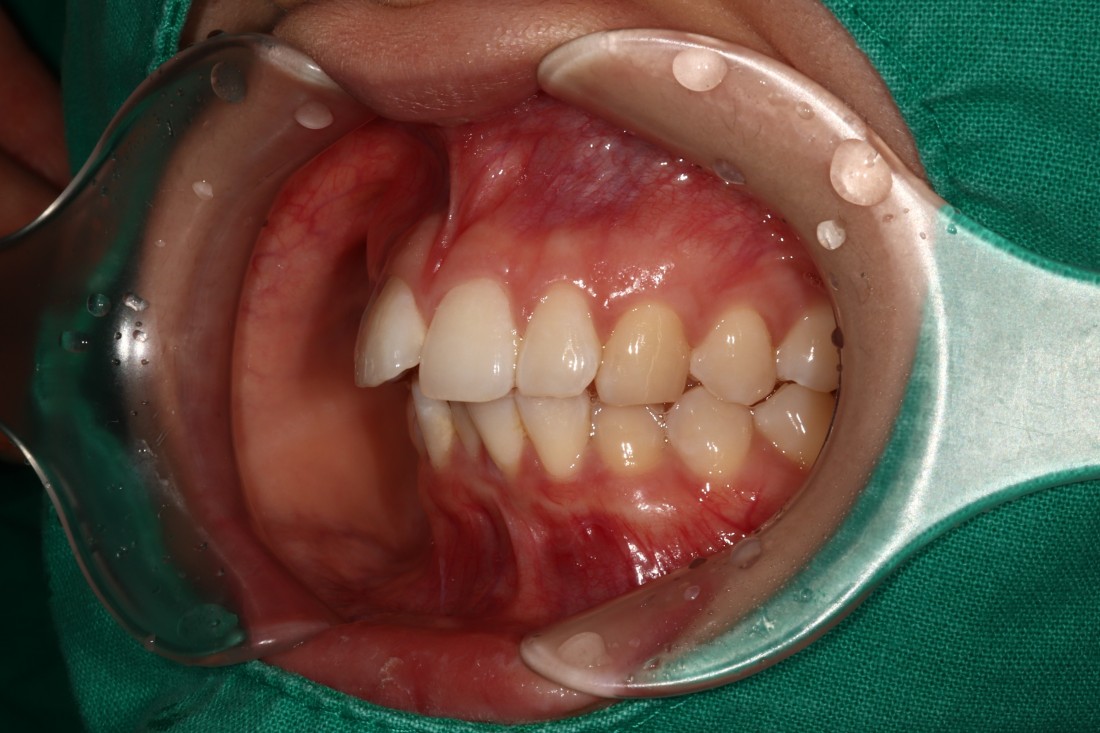

교정전문의만 있는 교정치과?

구강외과, 구강내과, 치아교정과 등

다양한 분과별 전문의 협진으로

충치치료부터 임플란트, 턱관절까지

동시에 진료하는 광주 교정치과 추천

광주 교정치과를 추천하는 이유는

교정전문의만 있는 교정치과가 아닌,

구강외과 / 구강내과 / 통합치의학과 등

다양한 분과별 전문의가 협진하기 때문에

전문의 치아교정 진료 뿐만 아니라

다양한 진료를 모두 동시에 받을 수 있기 때문입니다.

교정진료를 시작하기 전에

충치치료가 필요한 경우도 있으며,

임플란트를 식립하여야 교정진료의 효과가

더욱 우수해지는 케이스도 있습니다.

광주 교정치과 추천하는 곳에서는

분과별 전문의 협진 시스템을 통하여

개인별로 최적의 치료계획을 세워

최상의 치료결과를 얻을 수 있습니다.